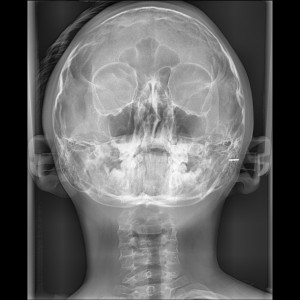

SIALOGRAFIA

• Glándulas parótidas y sub maxilares